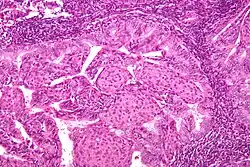

Pathology

- Epithelial tumors. For mesenchymal tumors, please see the uterine sarcomas page

- Most are well-differentiated, with proliferation of endometrial glands without intervening stroma

- Endometrial hyperplasia is thought to be a precursor lesion developed with unopposed estrogen and genetic events

- Simple vs complex hyperplasia based on glandular architecture

- Cytologic atypia increases risk of progression to carcinoma (complex atypical hyperplasia risk ~30%)

- Cells show microsatellite instability, PTEN, and k-ras mutations